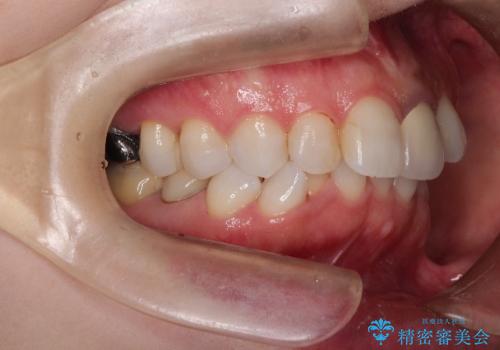

インビザラインによる非抜歯矯正 ガタガタな歯並びを整った歯並びへ

- 上下の全体的ながたつきが気になるとのことで来院されました。

マウスピースでの目立たない矯正を希望されたので、インビザラインでの治療となりました。

全体的に歯と歯の間にわずかに隙間を作り、歯を並べました。